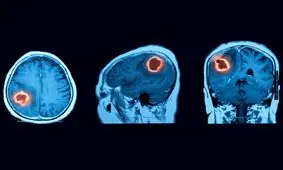

محقق ایرانی دانشگاه هوستون روشی جدید برای از بین بردن نوعی سرطان بدخیم مغز ارائه کرد که در آن از نوعی نانوحامل استفاده…